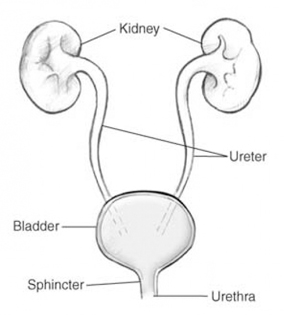

Kidney / Bladder Prostrate